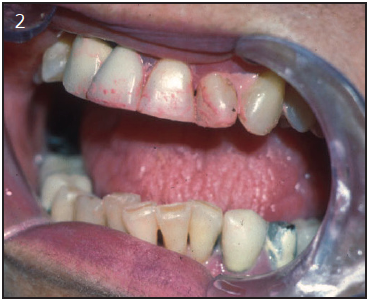

On examination, the patient with xerostomia due to reduced salivary gland function usually has obvious signs of mucosal dryness.1 The lips may be cracked, peeling and atrophic; the buccal mucosa pale and corrugated in appearance; and the tongue smooth and reddened with loss of papillation (Figure 1). The oral mucosa may appear reddened, thinner and more fragile. The patient may show signs of oral ulcerations, angular cheilitis, or complain of a burning sensation in their mouth and tongue known as stomatodyna.39 There is often a marked increase in erosion and dental caries, particularly at the gingival margin, and even cusp tip involvement. The decay may be rapid and progressive even in the presence of excellent oral hygiene (Figure 2). One should consider whether the caries' history and current condition are consistent with the patient's oral hygiene. Candidiasis, most frequently of the erythematous form, is frequent and may contribute to mucosal sensitivity (Figure 3). The salivary glands should be palpated for enlargement, changes in texture, sensation of pain, and also to determine if saliva can be expressed from the main excretory ducts. The saliva should be clear, watery and copious. A cloudy exudate may be a sign of bacterial infection, although some patients with very low salivary output will have opaque secretions that are sterile. After receiving radiation, saliva turns yellowish-brown in color, is thicker, and results in a more acidic pH.41

Figure 2 – The lips, tongue and all mucosal surfaces are dry in this patient with Sjögren’s syndrome. Note also the erosion and the presence of epithelial debris on the teeth, a sign of diminished salivary secretions.

Figure 2